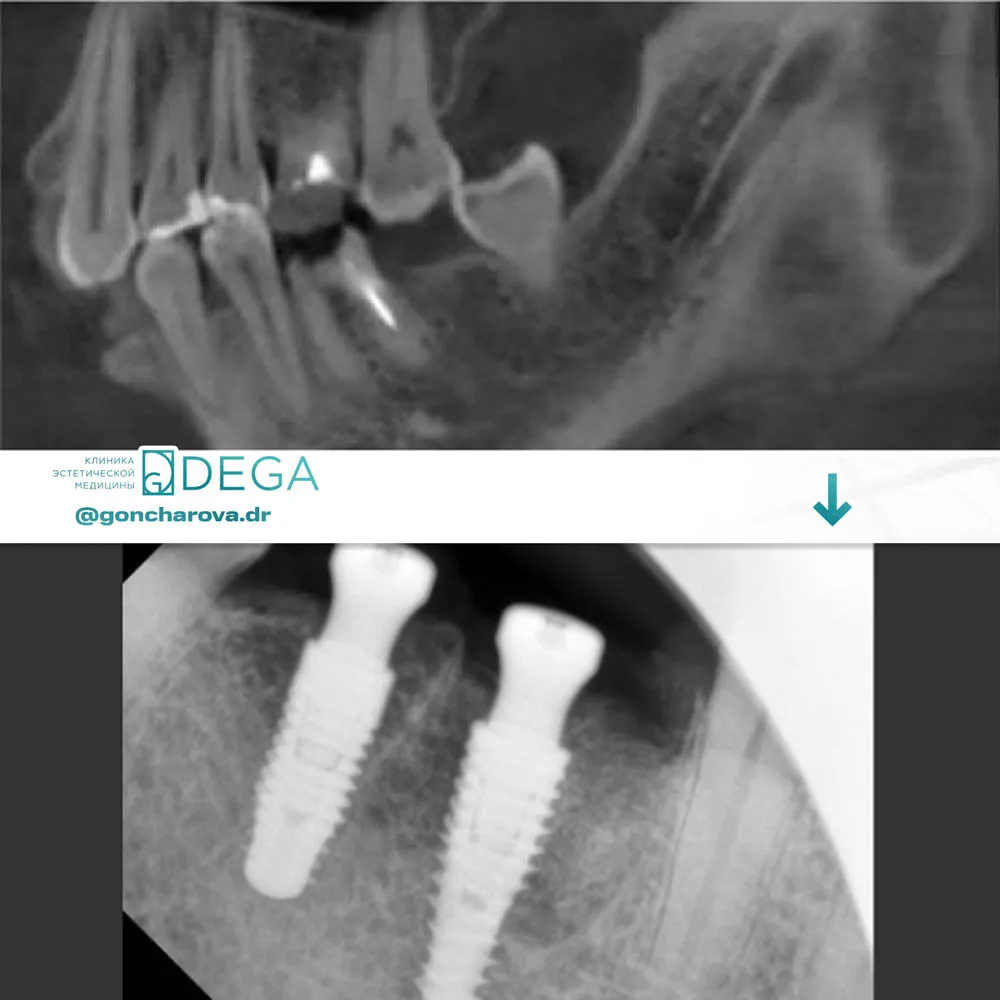

Имплантат — это основа для будущего протезирования, искусственный зубной корень, изготовленный из титана — биологически совместимого материала, который практически не отторгается организмом человека и не вызывает аллергической реакции. Специалисты клиники DEGA используют в своей работе имплантаты ведущих мировых производителей, качество и безопасность которых подтверждены многочисленными клиническими исследованиями.

Перед установкой имплантата необходимо пройти ряд исследований, на основании которых врач-стоматолог сможет составить последовательный план лечения. Диагностика включает в себя: биохимический анализ крови и компьютерную томографию. В случае, если костной ткани для фиксации имплантата достаточно, может быть выполнена одноэтапная имплантация, если нет — процесс будет осуществляться в два этапа.

- Собственно установка имплантата. Операция может выполняться как под местной, так и под общей анестезией. Врач делает небольшой разрез в десне и устанавливает имплантат в кость, после чего накладывает швы. Весь процесс занимает порядка 30-40 минут.